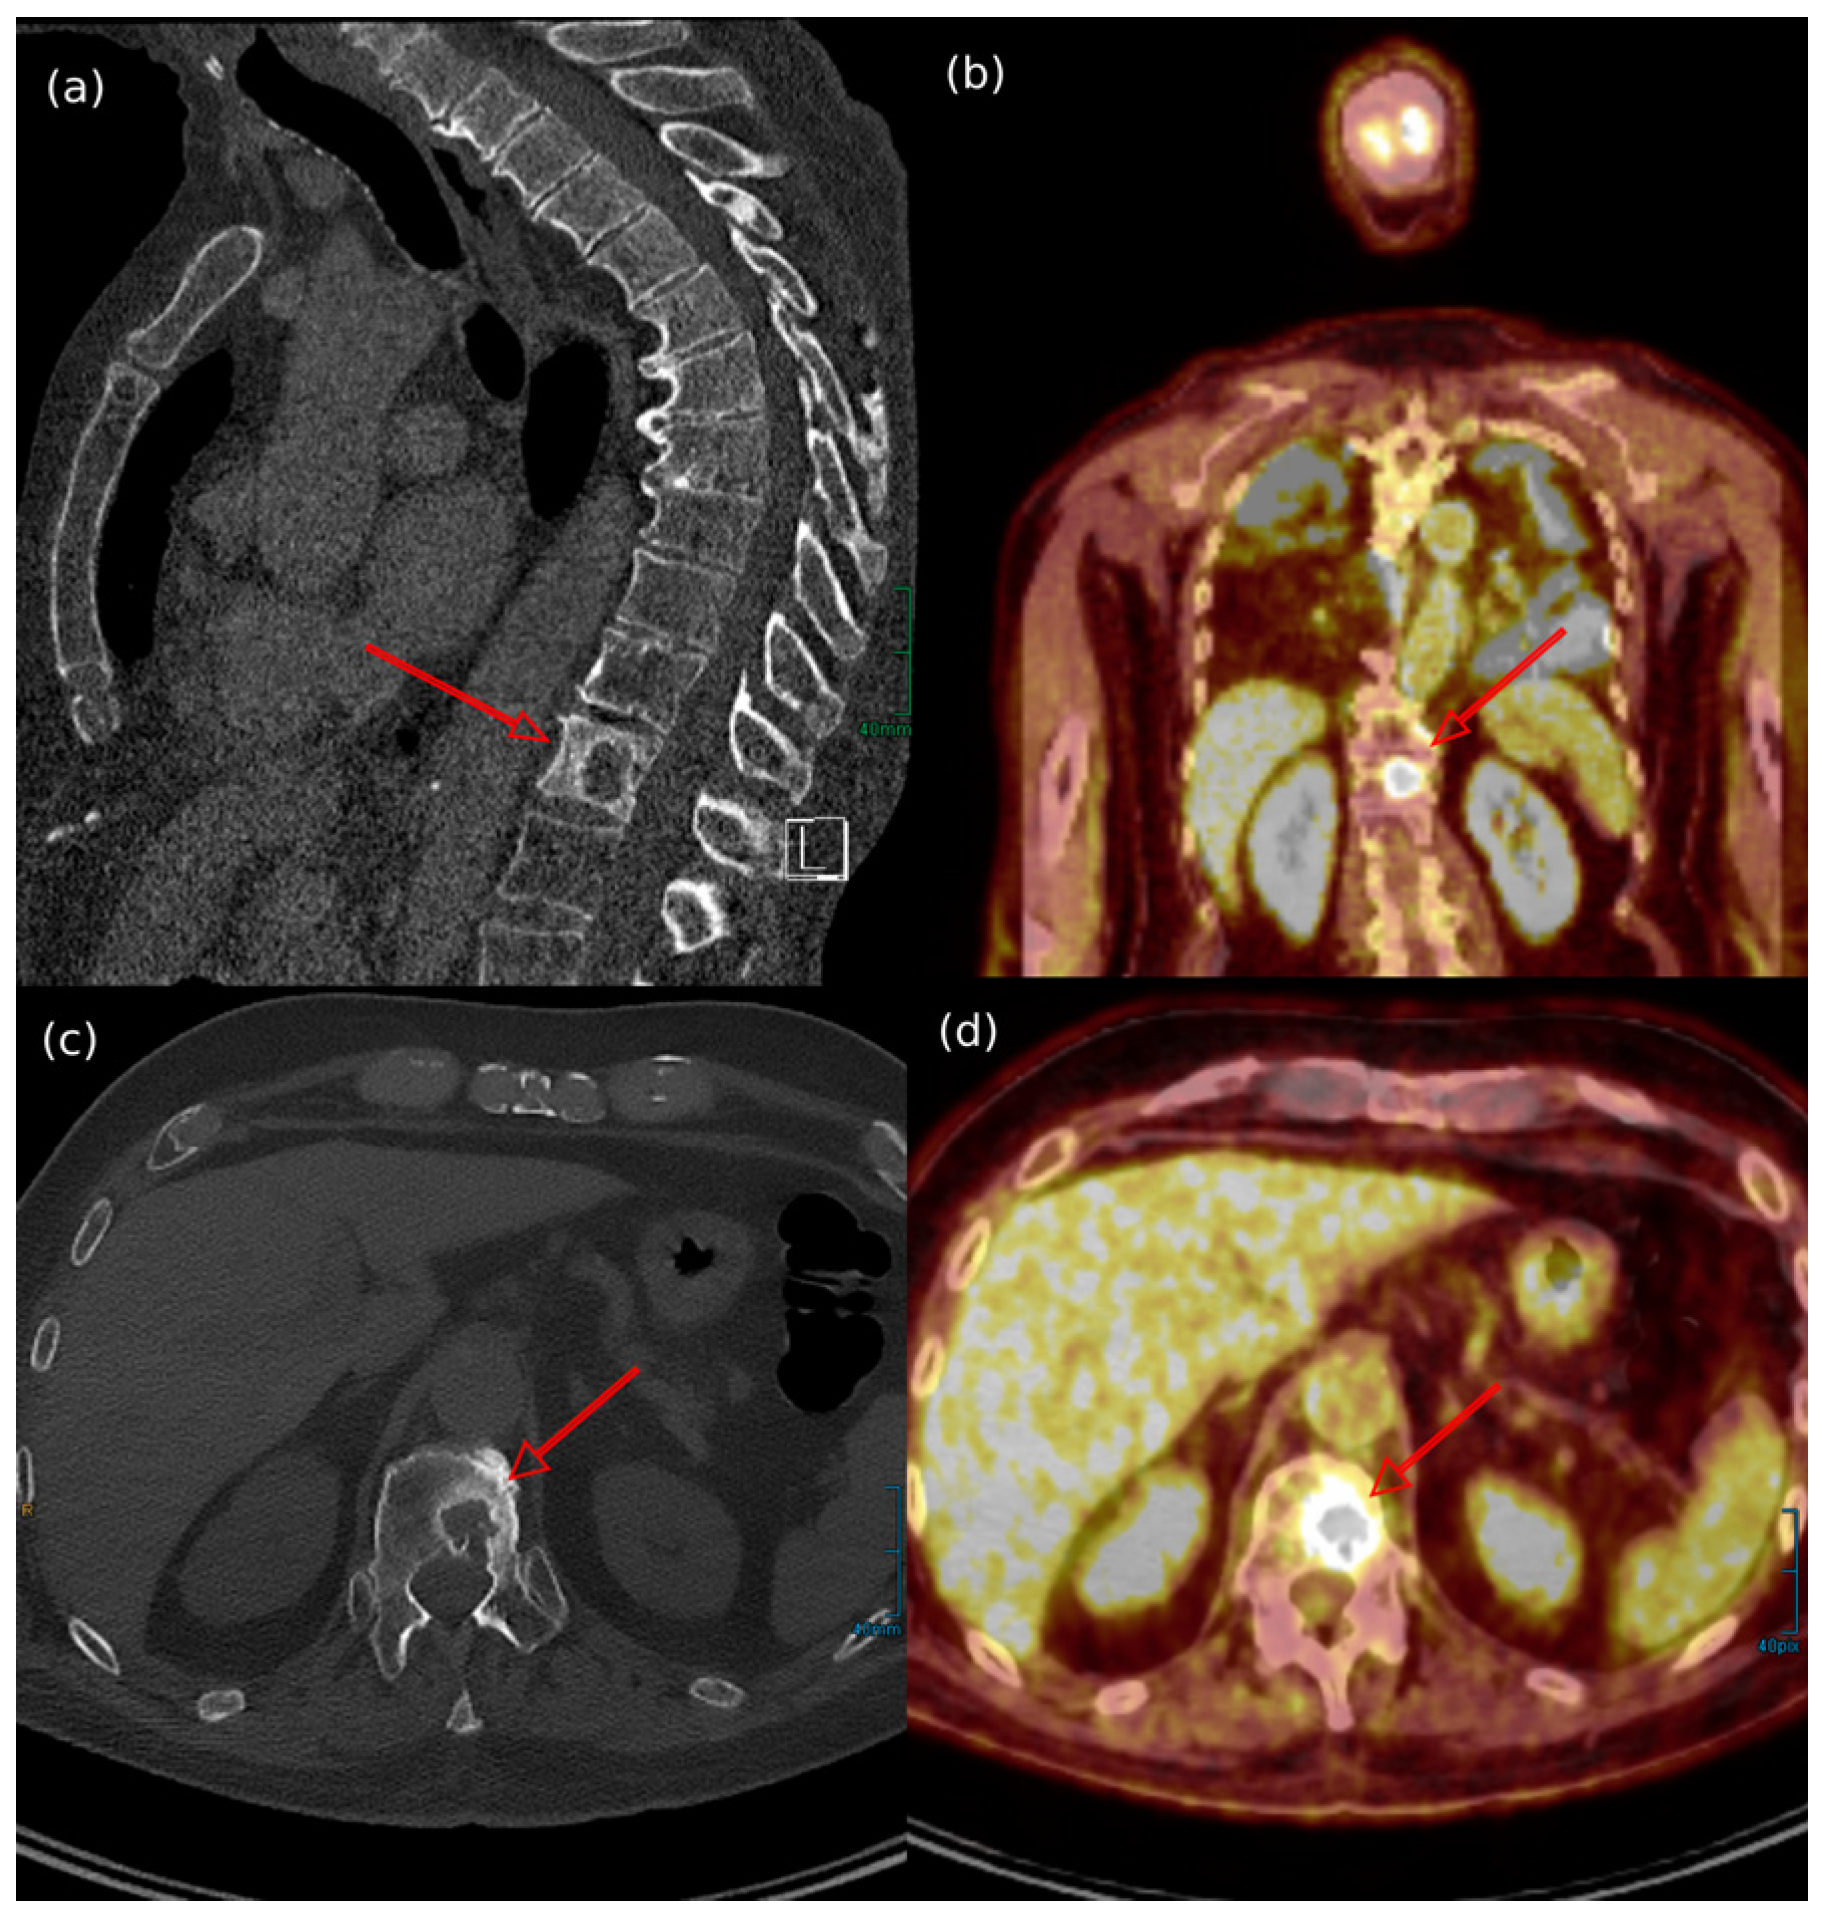

- Oh, H.Y.; Kim, D.; Choi, Y.S.; Kim, E.K.; Kim, T.E. Merkel Cell Carcinoma of the Trunk: Two Case Reports and Imaging Review. J. Korean Soc. Radiol. 2023, 84, 1134–1139. [Google Scholar] [CrossRef]